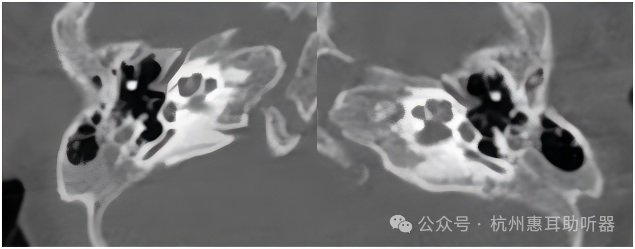

CT报告如下:

对于无法配合主观测试的婴幼儿而言,进行全面的气骨导ABR检查非常有必要,通过是否存在气骨导差判断听力损失性质,才能更精准的调试助听器。到西安惠耳后,听力中心就给汐汐进行气骨导ABR测试,显示存在气骨导差,便告知家长一定要进行CT检查,确诊孩子耳部结构异常的具体情况。除了ABR检查,宽频声导抗检查也同样是不可或缺的检查之一。目前的宽频声导抗除了鼓室图,还拥有鼓膜吸收率和共振频率,这对于中耳结构异常提示非常有意义。因此来杭州门诊后便复核骨导ABR,同时进行宽频声导抗检查,确诊存在气骨导差,并通过共振频率、鼓膜吸收率提示存在听骨链软连接情况,这一结论与其CT结果一致。针对汐汐外耳廓有一些卷曲,耳背式助听器佩戴容易滑落,同时耳模经常出现啸叫的情况,史主任详细和家长分析了听力情况,并推荐选配神逸3300CIC一对,佩戴后进行声场ABR测试,结果如下,家长当即表示非常满意,孩子能听到了,也不会像之前一样总是啸叫。同时也一定会牢记史主任的叮嘱,定期前来复查和更换定制机外壳。